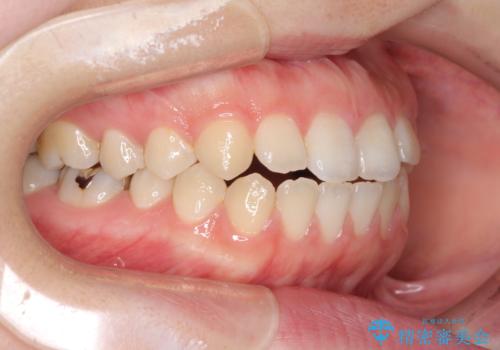

治療は順調に進み、予定された期間で終了することができました。

装置除去後には、スッキリとした口元となり、大変満足していただきました。